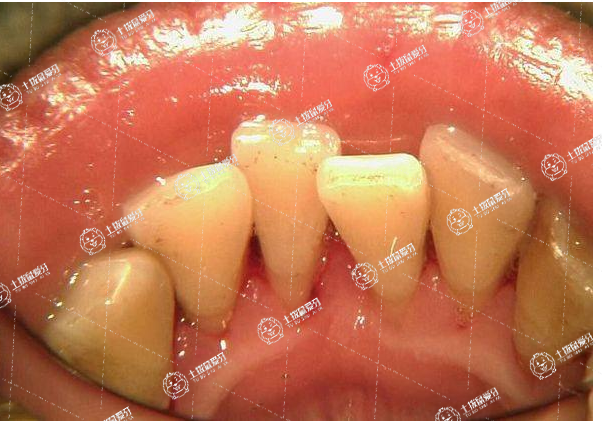

牙齒是幫我們咀嚼食物的工具,當然,也是承擔著整個面容美觀的。當牙齒如果有擁擠等情況的話,往往還會給身體健康帶來巨大的傷害,鑒于此,很多愛美人士往往在遇到牙齒擁擠后都會想辦法及時做矯正。牙齒擁擠矯正大概要花費多少錢?一起來了解一下。

牙列擁擠如果單純是牙齒引起,可以單純通過正畸治療解決。目前由于科學技術(shù)的發(fā)展,牙齒矯正包括各種不同的方法,具體如下: